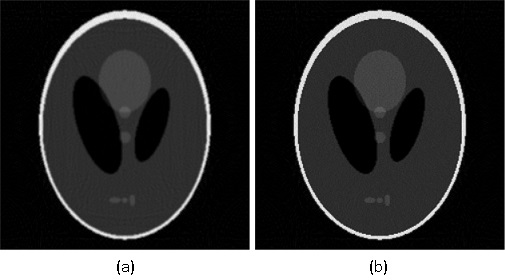

Given the problems we have pointed out regarding the first randomized algorithm, we have focused on the results obtained by the second randomized algorithm. For the parameters that we have fixed above, the results obtained by running the second randomized algorithm with 125000 iterations are given in Fig. 4 and Fig. 5 (Fig. 4 (a) is Fig. 2, and Fig. 5 (a) is Fig. 3). In both cases, the correction is significant, and the result of correction is very close in terms of reconstruction quality to the result obtained by running each of the two analytical algorithms alone with full view of 360 projection angles. That is, the result shown in Fig. 4 (b) is comparable to the result shown in Fig. 6, and the result shown in Fig. 5 (b) is comparable to the result shown in Fig. 7, which means a reduction in the number of views of (in Figs. 6 and 7 the reconstruction is more homogeneous, but with more visible artifacts). From the experiments we have conducted, we have remarked that the number of views can be reduced up to about and the results are still comparable to the results obtained by the analytical algorithms with full view, provided an appropriate number of iterations is chosen.